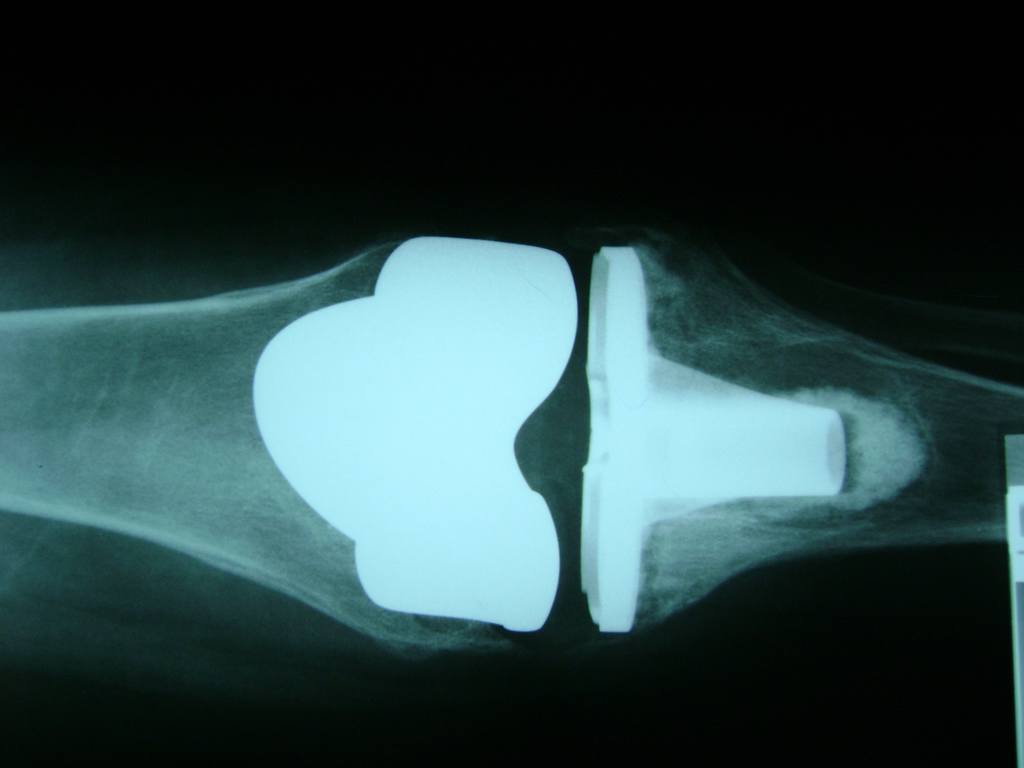

Cirugía de Fémur - Rodilla